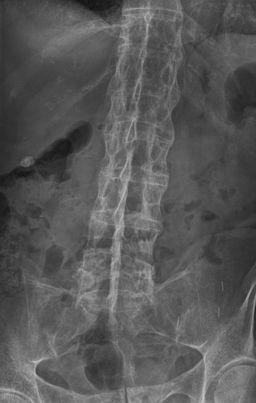

X-rays are the most helpful imaging modality in established disease, although they may be normal in early disease.

Look for sacroiliitis or enthesitis (particularly of the annulus fibrosus). Sacroiliitis initially shows as blurring in the lower part of the joint, then bony erosions or sclerosis occur and widening or eventual fusion of the joint.

The vertebral bodies may become 'squared'. In later stages, bony bridges (syndesmophytes) form between adjacent vertebrae, there is ossification of spinal ligaments and, in late disease, there may be complete fusion of the vertebral column (bamboo spine).

Bamboo spine

By Stevenfruitsmaak, via Wikimedia Commons